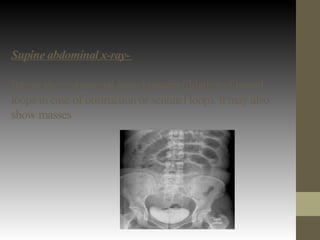

Supine abdominal x-ray-

It may show abnormal bowel pattern (dilation of bowel

loops in case of obstruction or sentinel loop). It may also

show masses